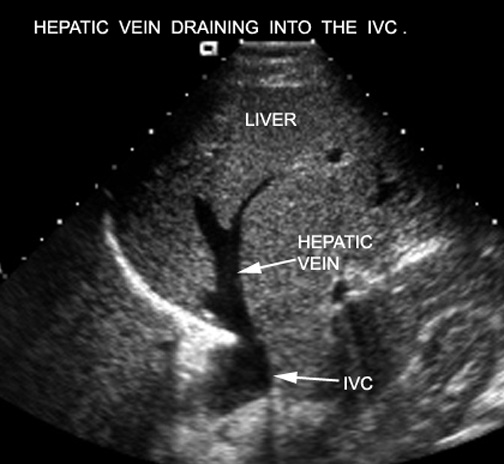

Hepatic veins draining into the IVC. Click the image for labeling.